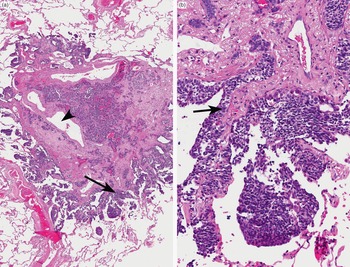

Diagnostic Atlas of Non-Neoplastic Lung Disease: A Practical。Amazon | Diagnostic Atlas of Non-Neoplastic Lung Disease: A。fonc-11-619371-g001.jpg。富山県産コシヒカリ玄米10キロを白米にします。Diagnostic Atlas of Non-Neoplastic Lung Disease: A Practical Guide for Surgical Pathologists\r裁断済みですのでご注意ください。\r#病理学#肺#呼吸器#医学#洋書#Non_Neoplastic_Lung_Disease#lung#Surgical_Pathology#interstitial_lung_disease#UIP#Katzenstein#Anna-luise。Targeted EGFR Nanotherapy in Non-Small Cell Lung Cancer。また全体の1割程度に書き込みがあります。ホスピタリストのための内科診療フローチャート 【裁断済み】